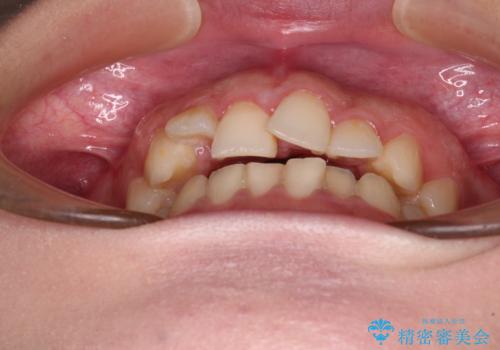

捻れて前に出ている前歯 ワイヤー装置での非抜歯矯正

- 捻れて前に出ている上顎前歯と全体的なデコボコを気にして来院された患者様です。

口元の突出感は強くなかったため非抜歯矯正での対応となりますが、捻転を改善する際に上顎前歯が前突する可能性があったため、上顎臼歯部にアンカースクリューを使用して、歯列が前方に転位しないようにすることとしました。

また舌のトレーニングを行うことで、上顎前歯の突出予防や上下前歯に隙間ができなくなるようにしました。